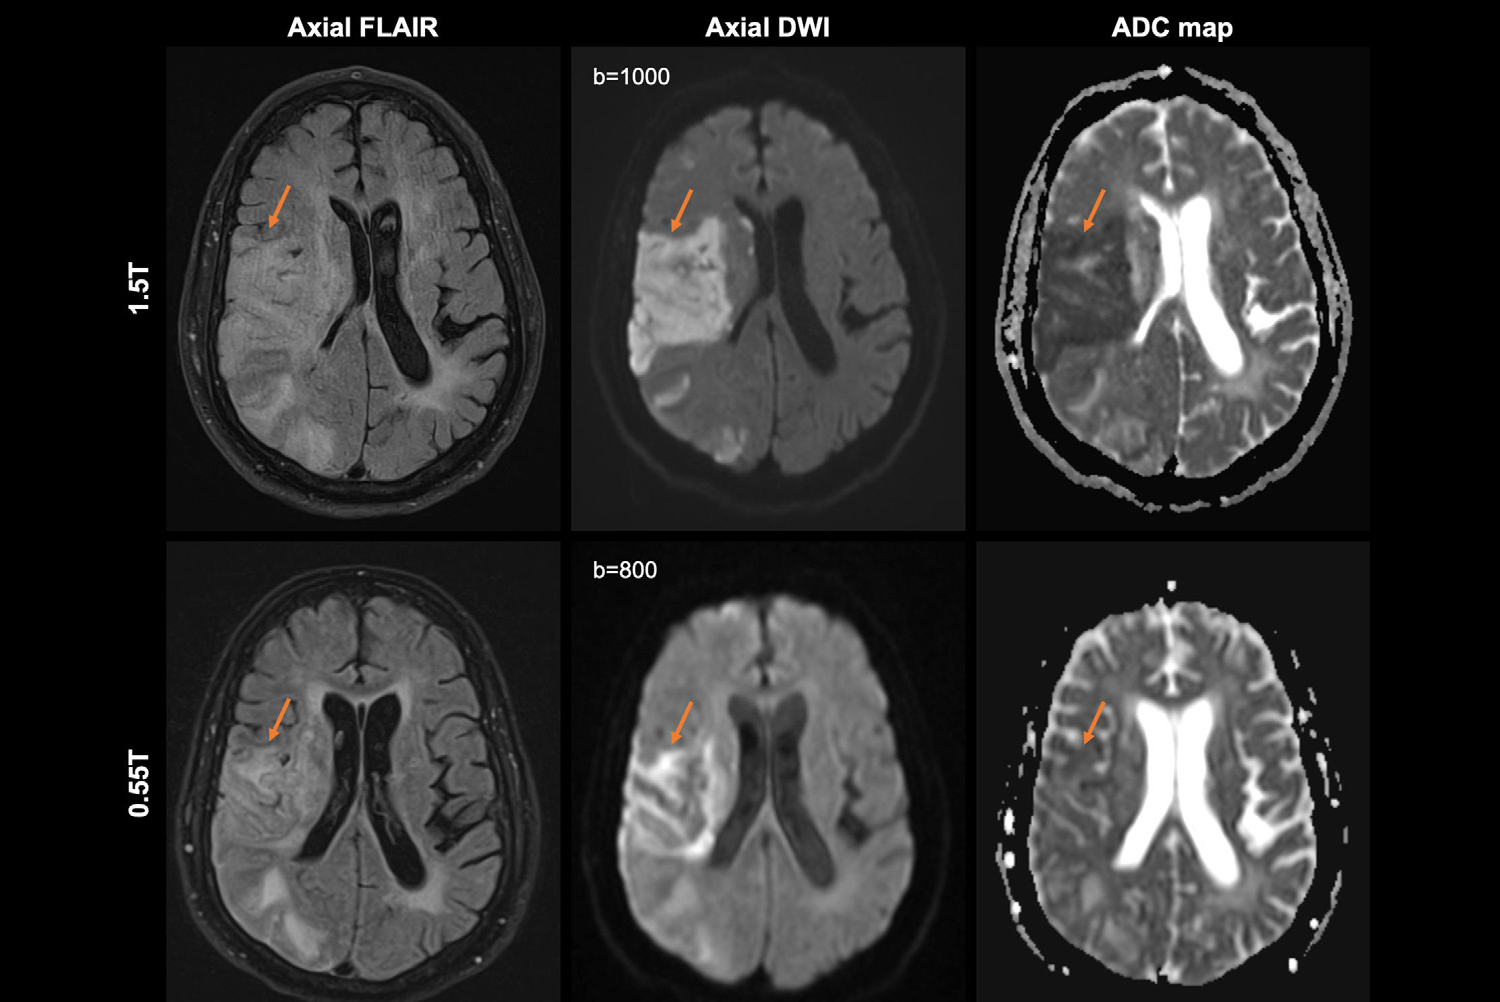

The results of the reader performance study demonstrated a mean of 2.2 and a standard deviation of 0.5 for overall image quality grading. Intraclass correlation was 0.44 after standardizing the image quality gradings. Sensitivity of pathology identification using 0.55T MRI was highest for consolidation (Reader 1) and reticulation (Reader 2). Both readers were unable to identify emphysema and pulmonary artery dilation, and had trouble identifying pulmonary nodules smaller than 8 mm. Thus, CT is better for detection of small nodules < 8 mm, but 0.55T MRI also has its strengths and potential applications, particularly for tumor recurrence detection.

CT has an advantage in detection of small pulmonary nodules compared to 0.55T MRI. A 7-year-old boy's three small pulmonary nodules (3 mm, 2 mm, and 3 mm) in bilateral lungs were detected on CT but not on 0.55T MRI. CT is still superior for detection of small nodules -- a limitation of 0.55T MRI.